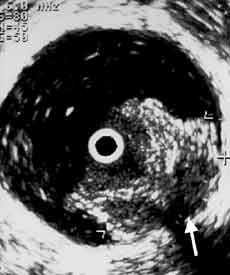

Рис. 4. Цистэндосонограммы. Рак мочевого пузыря стадия Т2а (стрелкой указана начинающаяся инвазия мышечного слоя). (Слева) Трансабдоминальное сканирование. (Справа) Эндовезикальное сканирование.